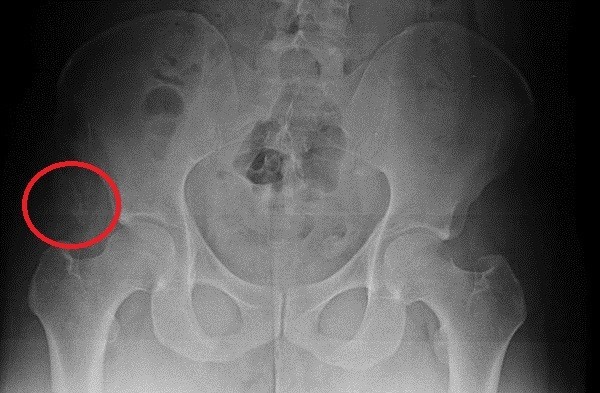

▲자생한방병원과 명지병원에서 촬영한 박주신 엑스레이 영상자료. 오른쪽 골반에 견열골절이 보여 두 사진은 같은 것으로 나타났다. ⓒ 뉴데일리DB이에 대해 명지병원 측은 다음과 같이 해명한 것으로 알려졌다.

▲ 박주신씨의 골반 부위 X-Ray 사진.ⓒ 뉴데일리DB

“오른쪽 엉덩이 쪽에서 골절된 뼈 조각을 찾았다.

저는 매일 같이 뼈만 보는 사람이다.

사진을 들여다보고 있으면 어느 정도의 정황을 유추할 수 있다.엑스레이를 보면 청소년기에 근육이 붙는 자리 쪽 오른쪽 골반 뼈에, 견열골절(인대가 손상되면서 뼈조각이 떨어져 나간 것)이 왔다.

이 엑스레이의 주인이 아주 험하게 살았다고 단정하는 이유다.”